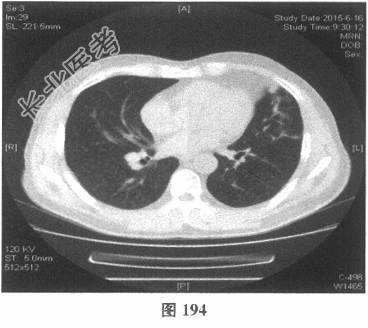

- 多项选择题4.[提示]患者应用多种抗生素治疗(第三代头孢菌素、青霉素加酶抑制剂)包括抗曲霉菌治疗无效,加用甲泼尼龙40mg静脉滴注病情好转。肺部CT检查显示病变明显改善。尿常规检查正常, 肾功能检测正常。复查肺部CT(图188~图195):示病变较前好转。Wegener肉芽肿的主要临床表现是( )

C、肺部CT常见肺内多发团块状影,常见空洞